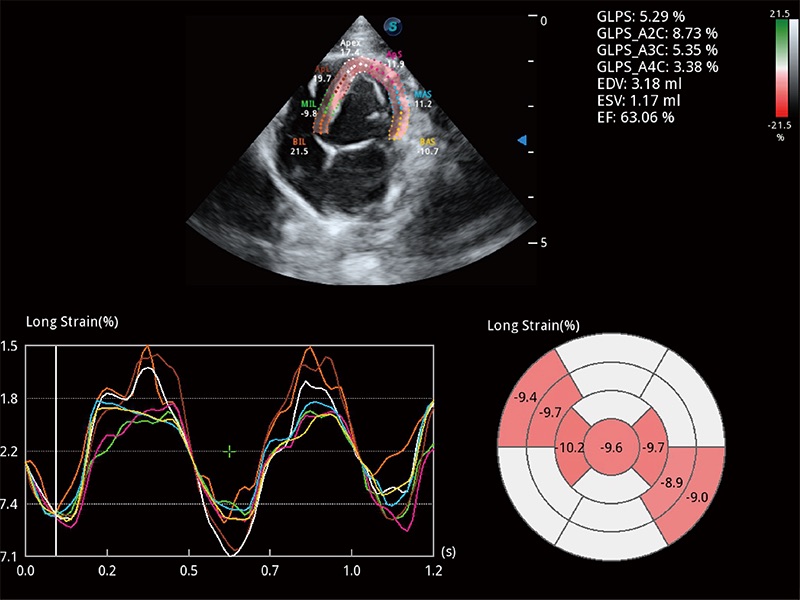

通過(guò)心肌識(shí)別技術(shù)與二維斑點(diǎn)追蹤技術(shù)相結(jié)合,對(duì)心臟的超聲圖像進(jìn)行量化分析。計(jì)算心肌17個(gè)節(jié)段的應(yīng)變、應(yīng)變率、速度、位移等,并通過(guò)牛眼圖的形式進(jìn)行呈現(xiàn)。

實(shí)時(shí)用顏色表示心肌組織運(yùn)動(dòng),觀察和定量組織的運(yùn)動(dòng)情況,對(duì)快速檢測(cè)與評(píng)估心肌的灌注和活性、電傳導(dǎo)及心肌收縮和舒張功能等均能提供重要的診斷信息。